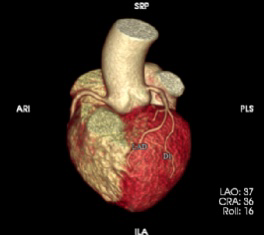

特色项目:(1)CT下肢动脉血管成像(CTA);通过增强血管成像,可清楚显示并明确动脉血管病变范围、程度和性质,如下肢动脉狭窄,闭塞等。(2)心脏冠状动脉CTA:通过增强检查,可显示多种心脏疾病,分析冠脉斑块成分及狭窄程度。(3)CT定位下穿刺活检:在CT引导下对病变部位进行穿刺,取病变组织用于病理检查,明显病变性质。常用于胸部、肝脏、肾脏、骨骼等部位。